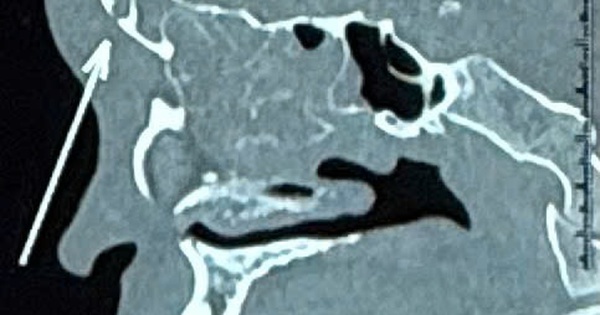

Tưởng chỉ viêm xoang đơn giản, nam thanh niên suýt mất mạng vì bị biến chứng

(NLĐO)- Từ triệu chứng “bình thường” của viêm xoang như chảy mũi mủ, đau đầu vùng trán, nam thanh niên này đã chủ quan tự uống thuốc tại nhà